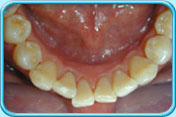

清除黑漬後的牙齒預防方法

清除橙色漬後的牙齒預防方法

每天早晚刷牙和使用牙線徹底清除牙菌膜,以保持牙齒潔白。